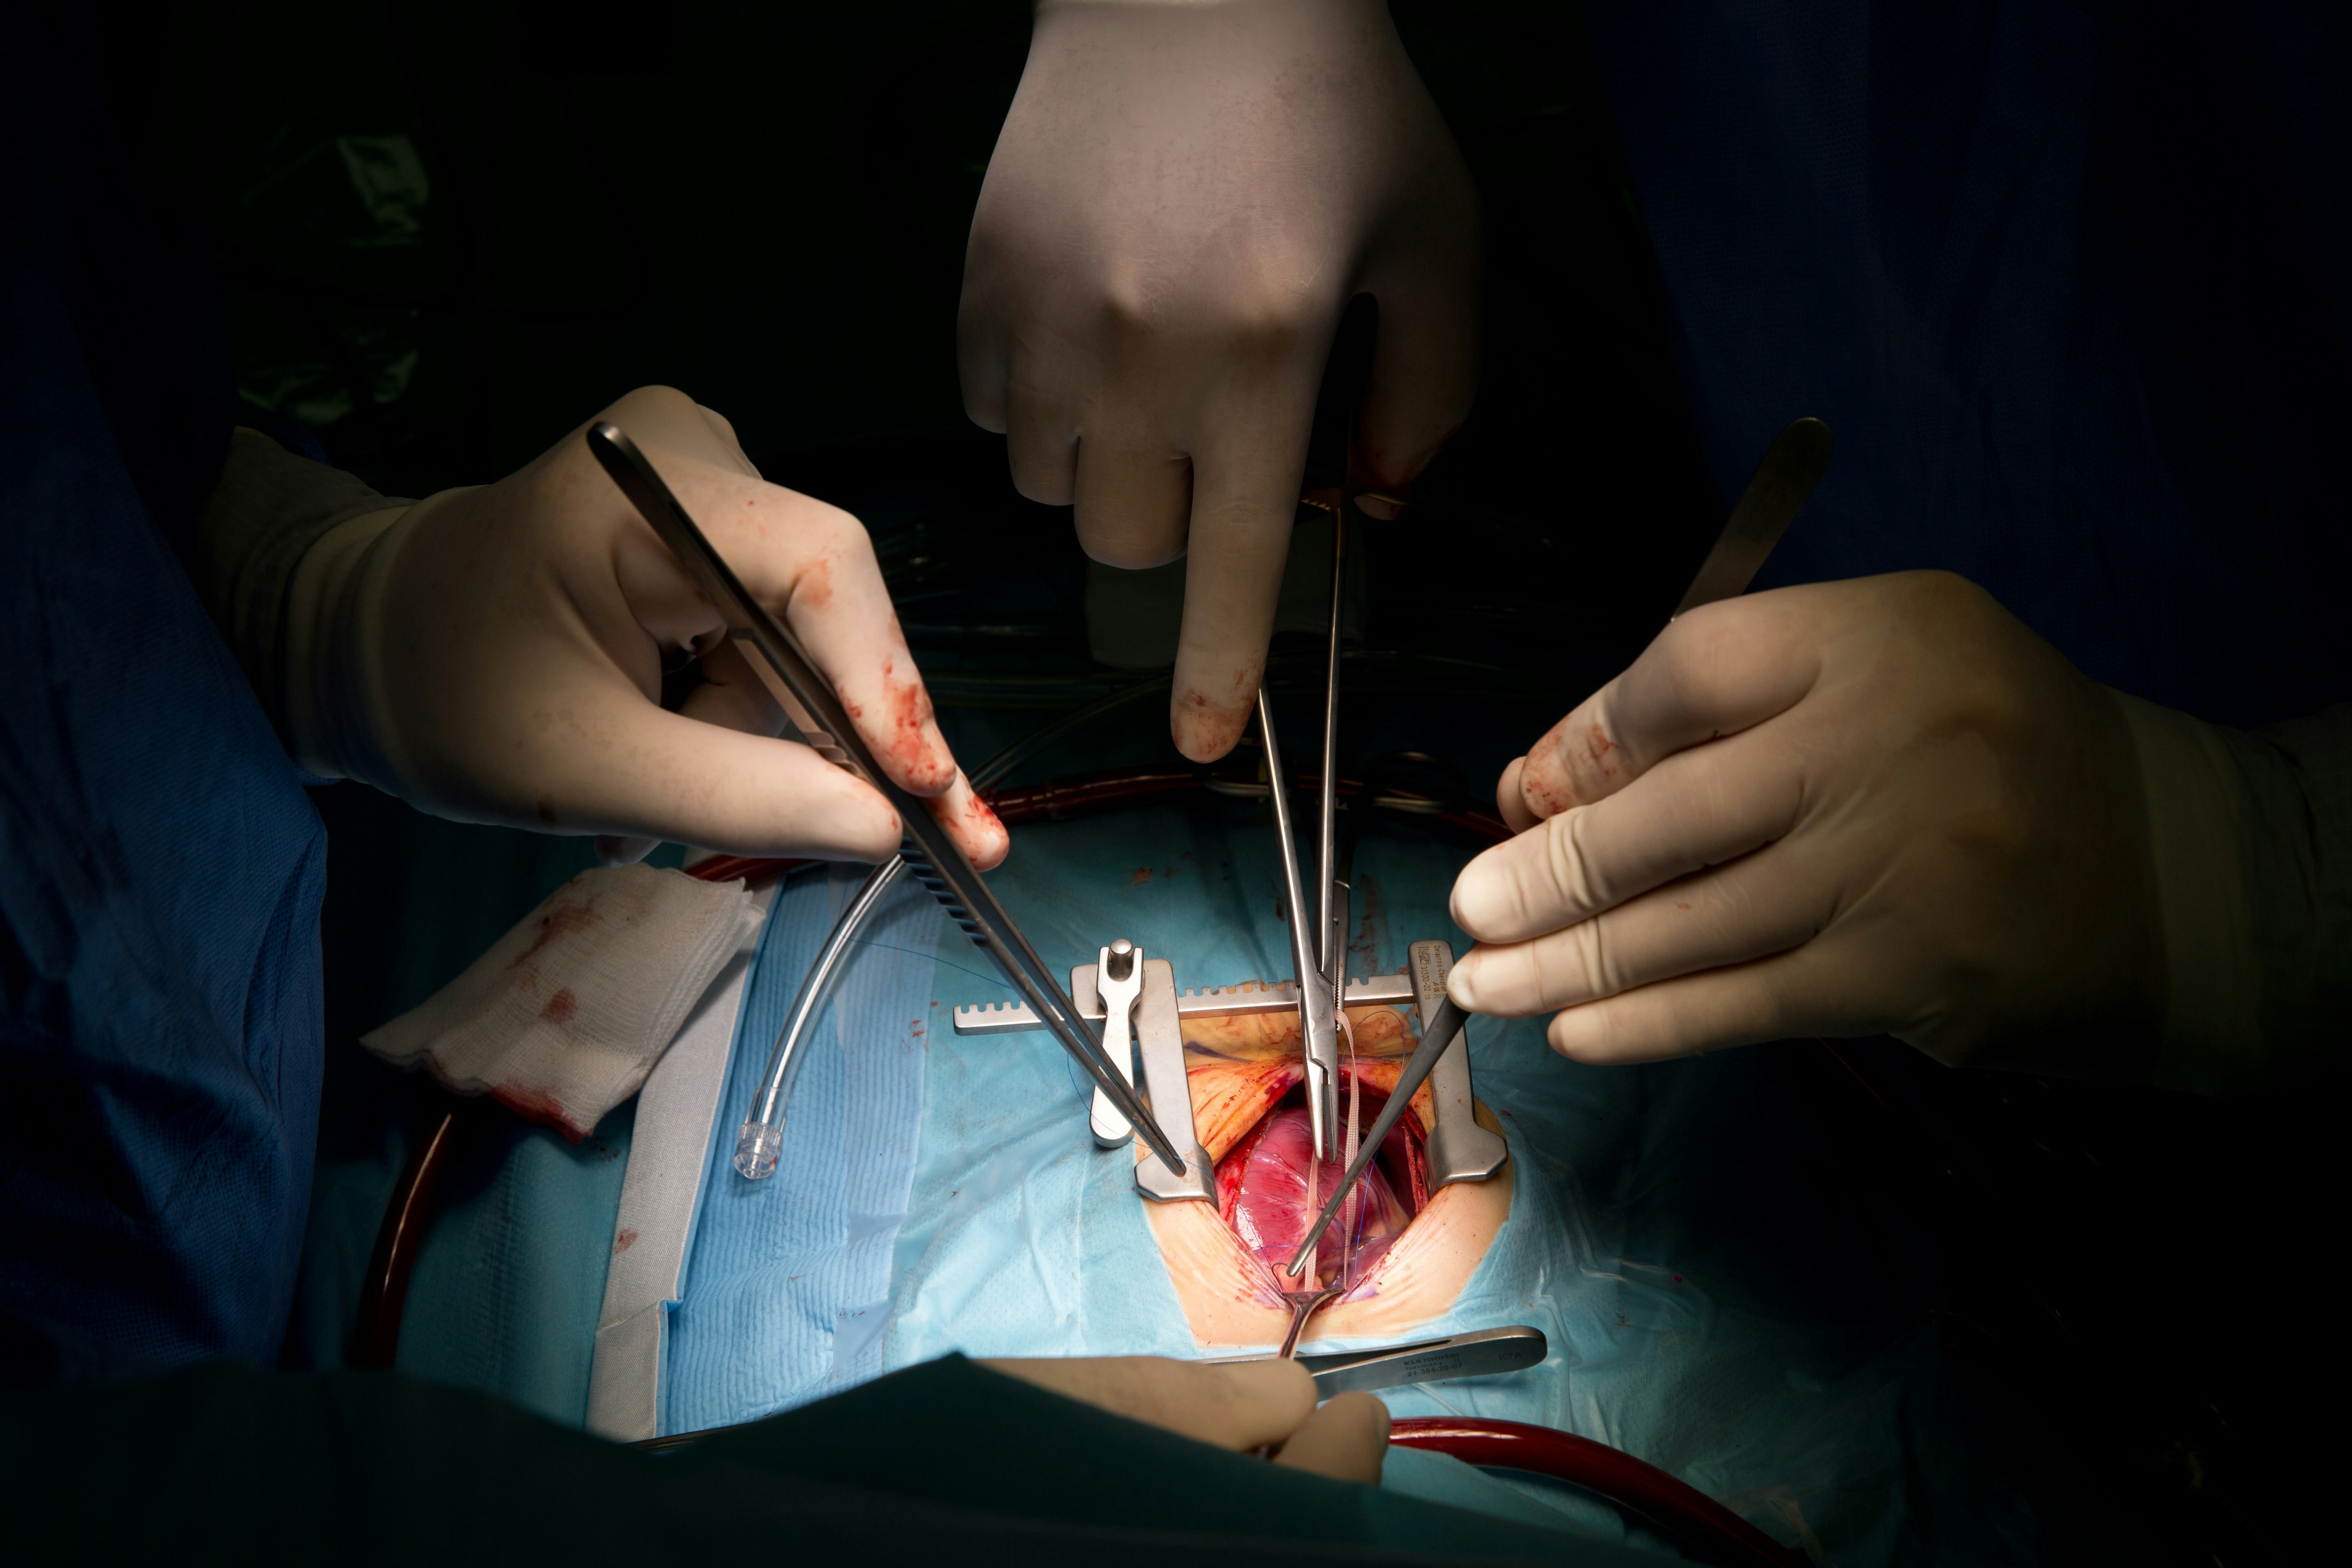

Bridging the gap between world-class medical expertise and global patients. High-precision surgery at lower costs than Western alternatives.

"Independent clinical audits ensure the highest surgical success ratios."